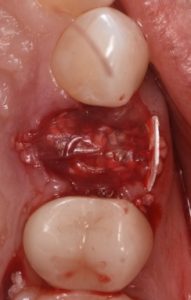

This video demonstrates alveolar ridge preservation following atraumatic surgical extraction of an endodontically treated tooth. Emphasis is placed on minimizing surgical trauma to preserve existing hard and soft tissues.

The case features flap management in the presence of a buccal dehiscence, followed by bone graft placement and stabilization using a dense polytetrafluoroethylene (d-PTFE) membrane. Surgical principles, membrane selection, and handling techniques are discussed to optimize ridge dimensions and facilitate future implant placement.